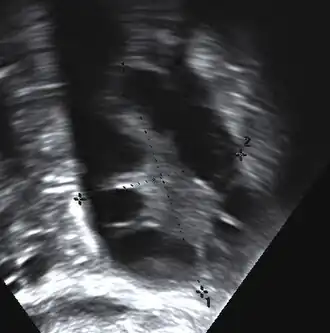

A polycystic ovary

The syndrome acquired its most widely used name due to the common sign on ultrasound examination of multiple (poly) ovarian cysts. These "cysts" are immature ovarian follicles. The follicles have developed from primordial follicles, but this development has stopped ("arrested") at an early stage, due to the disturbed ovarian function. The follicles may be oriented along the ovarian periphery, appearing as a 'string of pearls' on ultrasound examination.[63]

Gynecologic ultrasonography first looks for small ovarian follicles.[75] To count as polycystic ovaries, at least 20 follicles need to be present, smaller than 9 mm. This used to be 12 in older diagnostic criteria.[16] A less clear marker of PCOS is enlarged ovaries.[75] Ovary need to be at least 10 cm3 to count.[16] For sexually active individuals or those that agree, a transvaginal ultrasound approach is preferred. Alternatively, AMH levels can be tested in the blood.[75] Laparoscopic examination may reveal a thickened, smooth, pearl-white outer surface of the ovary. This would usually be an incidental finding if laparoscopy were performed for some other reason, as it would not be routine to examine the ovaries in this way to confirm a diagnosis of PCOS.[78]